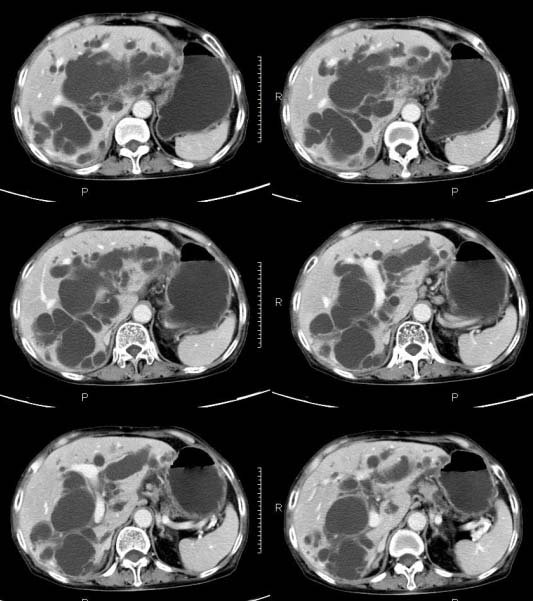

女,71岁,腹痛、腹胀、黄疸20余天,b超示肝内外胆管高度扩张内伴絮状物质(未提示梗阻部位或结石影),经抗炎解痉治疗后,肝功能有所好转,但胆道梗阻状态并未减轻。患者曾于1970年代做过胆囊切除术,1997年因胰腺炎而手术;且患者有糖尿病10余年。ct图片传了静脉期,未传动脉期了,最后一序列为3.2mm薄扫,请各位同仁仔细看看,确定一下胆管梗阻的部位,是炎性梗阻还是肿瘤性梗阻,是否与胰腺炎有关系,扩张胆总管中段前缘是否是胰管。请高手们最好用图示来指出梗阻部位。

请大家看看扩张的胆总管内见一弧线形间隔,怎样解释?

先天性胆总管囊肿伴肝内外胆管扩张!

肝内外胆管显著扩张,考虑先天性胆管囊肿(ⅳ型)。

肝内胆管远侧、近侧不比例扩张,以近侧为明显。胆总管扩张。考虑先天性胆管囊肿(ⅳ型)。